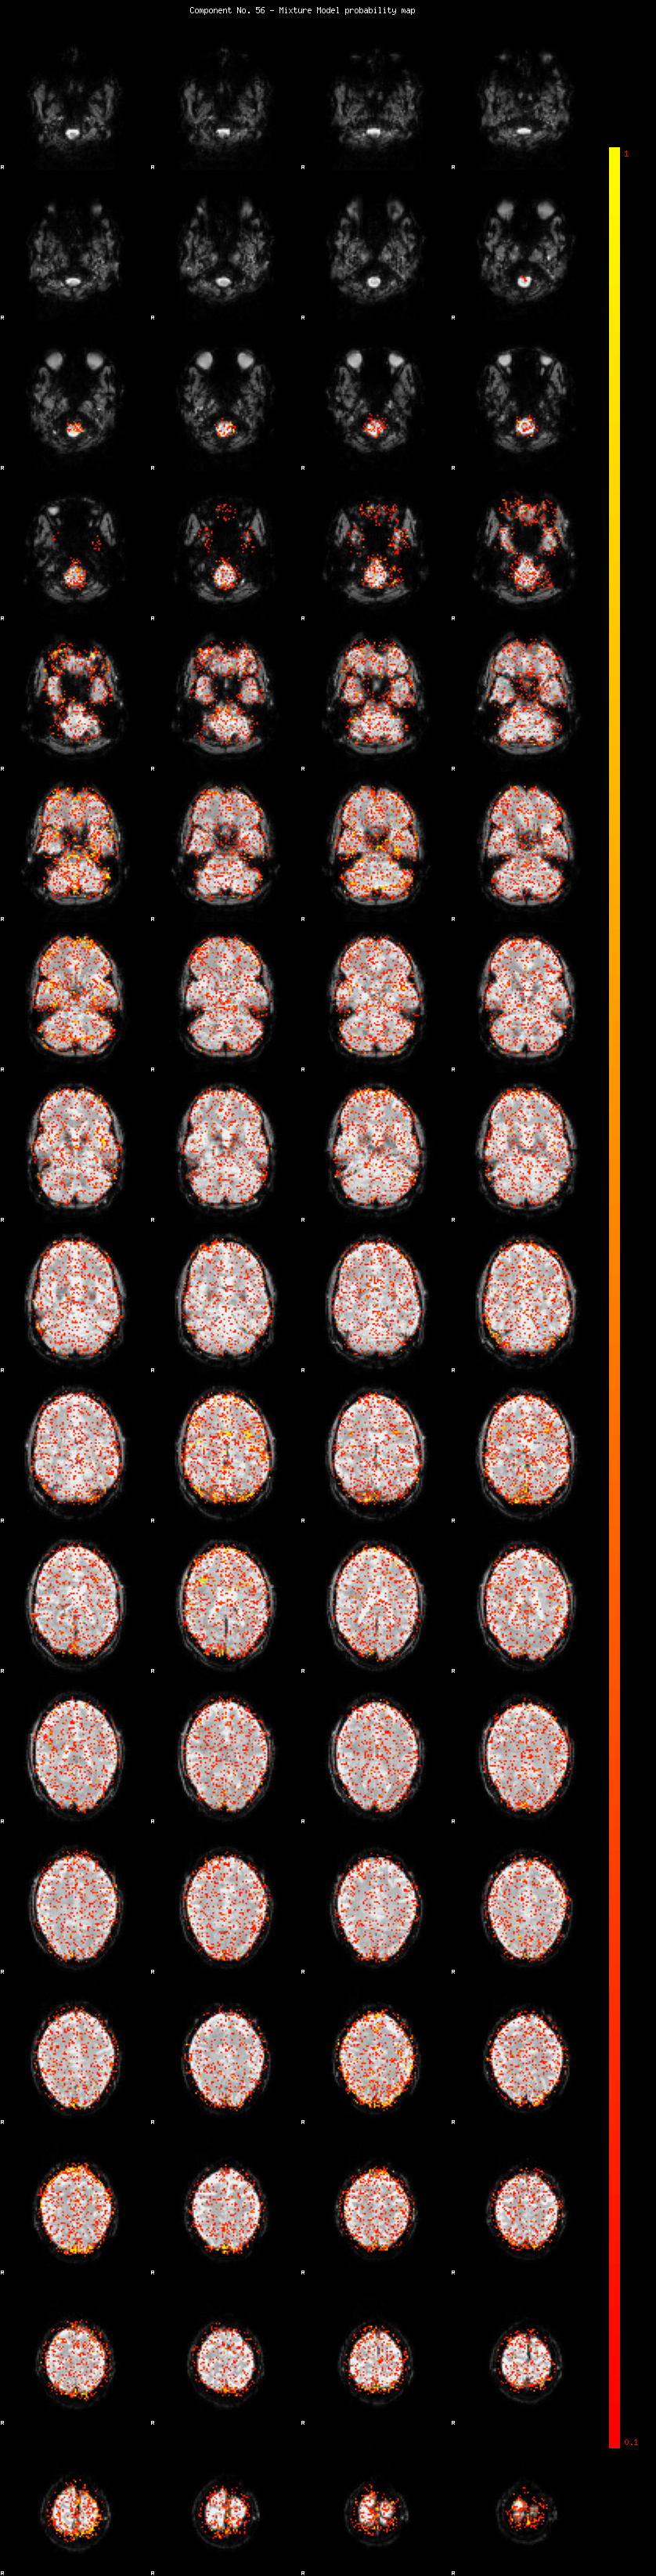

IC_56 Mixture Model fit

Means : -0.000000 2.095913 -2.055620

Vars : 1.000000 0.895439 0.793458

Prop. : 0.930974 0.033610 0.035416